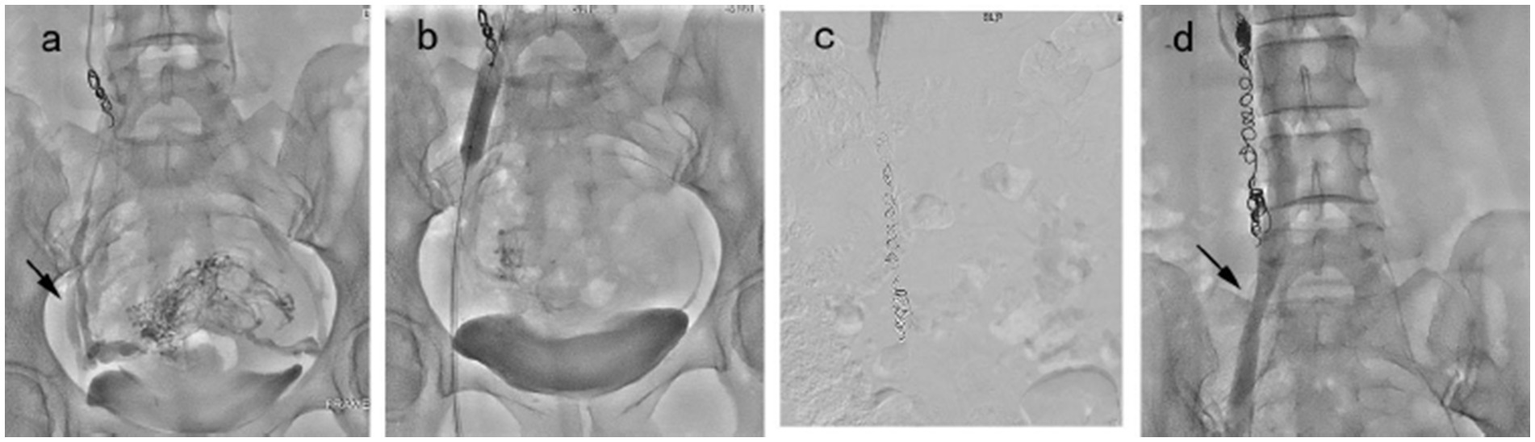

Figure 3

Embolization procedure in a 43 year-old patient was diagnosed with VO-CPP. (a) Congestion of the pelvic venous plexus and opacification of bilateral internal iliac vein (black arrow). (b) A balloon catheter was placed in the right internal iliac vein to prevent the return of the foam hardener until blood flow was reduced significantly. (c) Right ovarian vein embolization was performed using the sandwich technique. (d) The balloon catheter was withdrawn, and angiography showed no abnormality (black arrow).